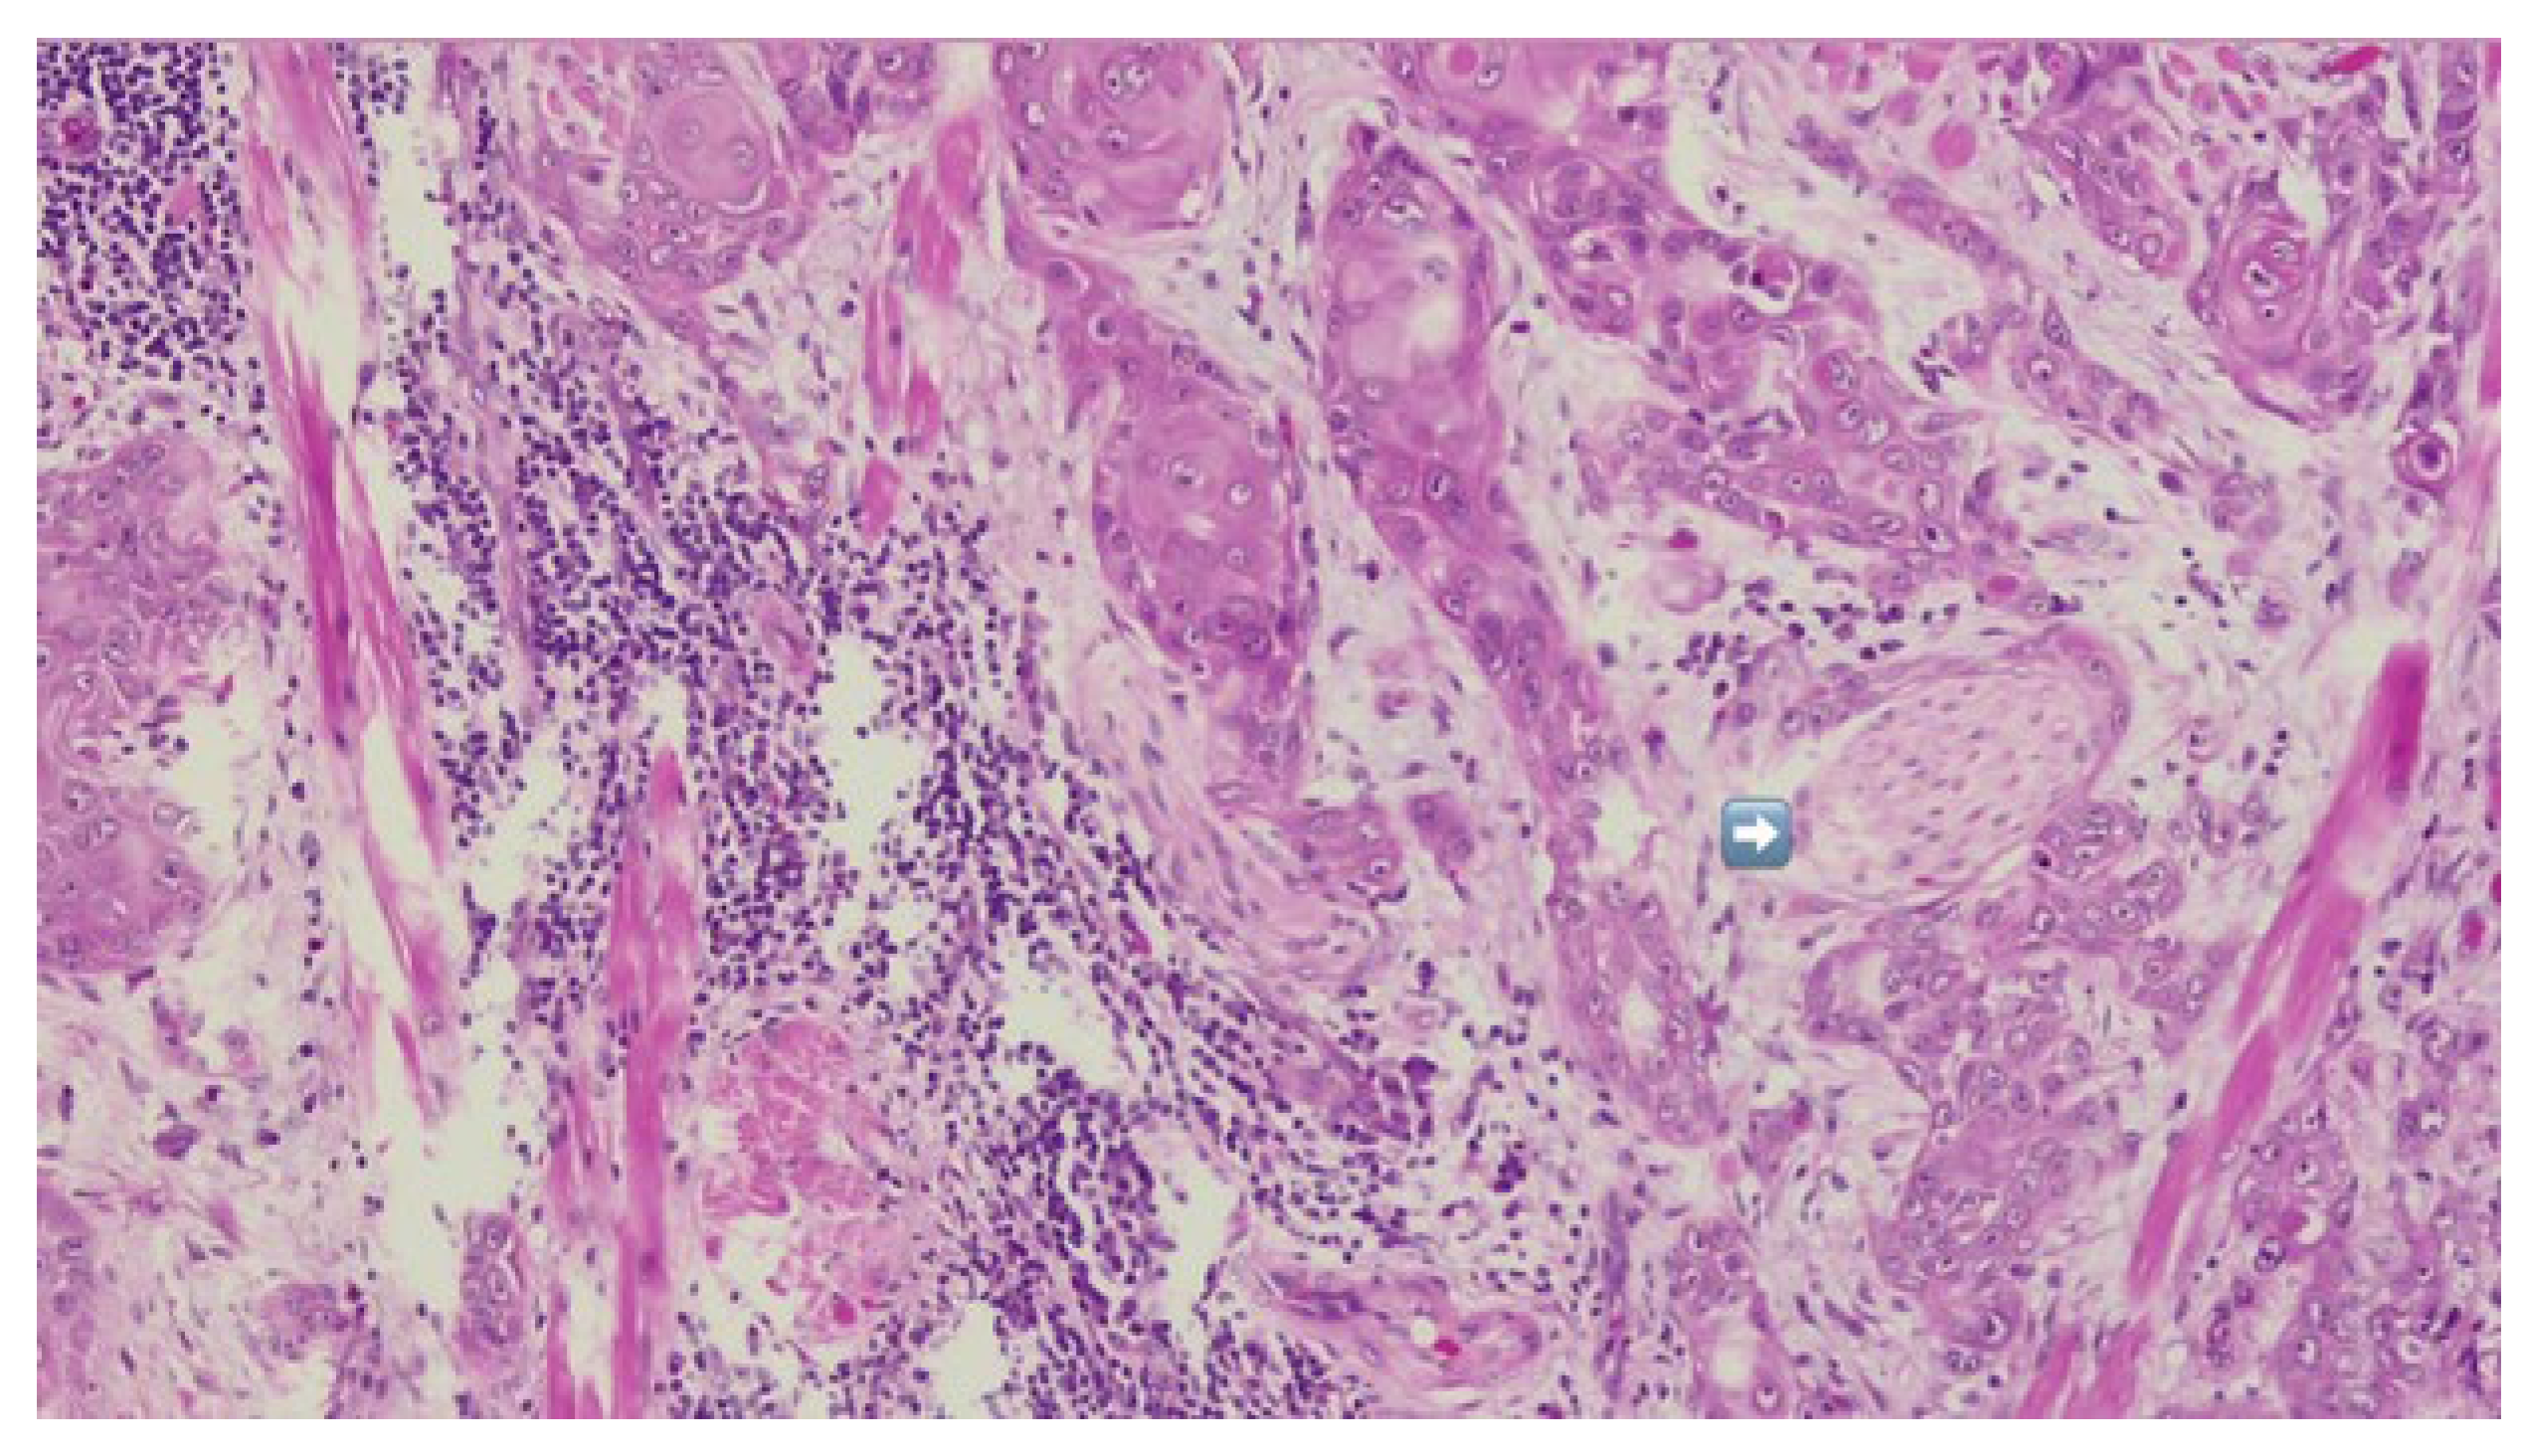

The patient was referred to the Department of Oral and Maxillofacial Surgery for further evaluation and management. Following an outpatient consultation and comprehensive clinical examination, no palpable cervical lymphadenopathy was identified on physical assessment. Incisional biopsy of the oral lesion was performed under local anesthesia and the histopathological analysis of the biopsy specimen subsequently confirmed the diagnosis of moderately differentiated keratinizing squamous cell carcinoma grade II Immunohistochemical staining for p16 was also performed and showed a negative result, indicating that the lesion was not HPV-related but more consistent with a conventional, tobacco-associated carcinogenesis pathway (Figure 2).

Figure 2.

Biopsy-immunohistochemical reaction-p16 marker-negative.

Definitive histopathological analysis of the surgical specimen confirmed a moderately differentiated keratinizing squamous cell carcinoma with evidence of perineural invasion (Figure 7). All surgical margins were free of tumor infiltration (R0 resection). Examination of the lymph nodes removed during selective neck dissection revealed no metastatic involvement (0 nodes). No evidence of distant metastasis was identified on preoperative imaging or postoperative staging, confirming a final pathological stage of pT3N0M0 (Stage III) according to the AJCC 8th edition.